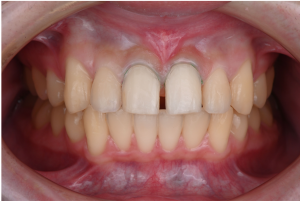

※治療終了時

歯並びが整い、あわせて形にバランスの乱れがあった上の前歯2本は、ラミネートベニアによって自然な見た目に整えられました。

※治療終了時の口腔内写真(正面)

歯科技工士が作製した補綴物は、周囲の歯になじむ自然な見た目に仕上がっています。

※術前(左)と術後(右)

治療後の結果について、患者さまから前向きなお声をいただいています。

※口元の拡大

口元の印象も、自然でバランスの取れた状態となりました。